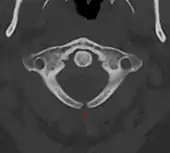

کمان مهره اطلس و زائده دندانی مهره آسه در تصویر سی تی.